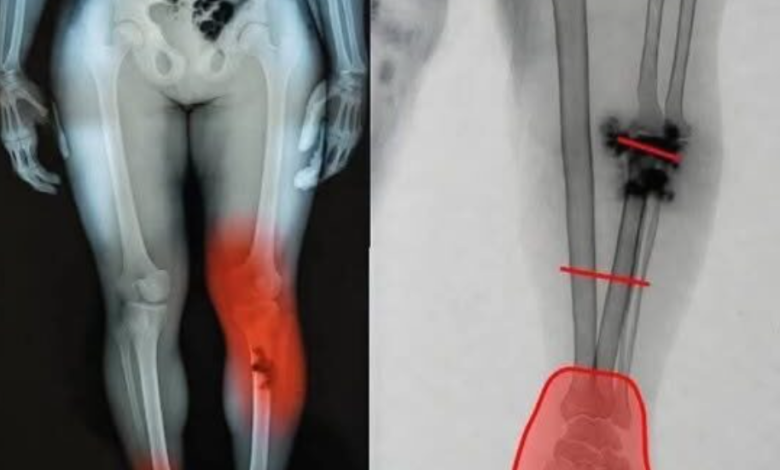

The images in question typically depict lower leg and foot trauma, showing shattered bone structures or mysterious “growths.” While the visuals are undeniably distressing, radiologists and orthopedic specialists have been quick to intervene. Upon closer inspection, these X-rays do not show the systemic cellular response one would expect from a pharmaceutical side effect. Instead, they display the hallmark signatures of localized trauma, advanced untreated infections (such as osteomyelitis), or severe vascular compromise—conditions that existed long before the advent of mRNA technology and are entirely unrelated to the mechanics of vaccination.

To the untrained eye, a dark spot or a jagged line on an X-ray is a sign of catastrophe. To a specialist, it tells a specific story. Dr. Elena Rodriguez, a senior radiologist, notes that the images being circulated as “vaccine damage” are actually clinical examples of late-stage diabetic complications or high-impact fractures. “Bones do not simply disintegrate or shift because of an immune response,” Rodriguez explains. “The pathologies shown in these viral posts are the results of years of underlying disease or sudden, violent physical force.”